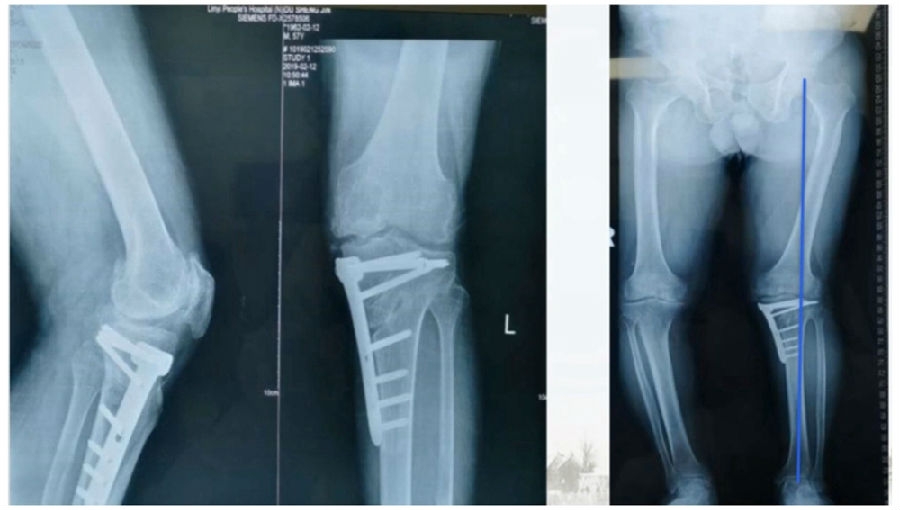

术后检查证实达到了术前预期的手术效果,关节线达到了平行,半脱位得到矫正,同时关节线和地面水平。病人行走达到了理想的效果。

术后X线

患者术后4个月截骨愈合,膝关节稳定维持得非常好。

术后4个月